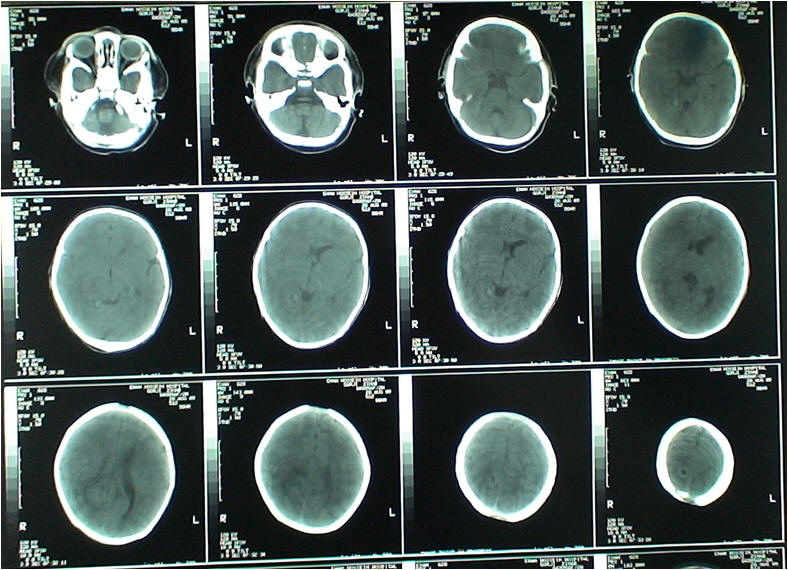

معرفی بیمار

بیمار دختر 52 روزه ای است که با شکایت تب بالا و

poor feeding

به بیمارستان امام حسین در خرداد ماه 1388

ارجاع شده بود، قبل از مراجعه علائمی مانند اسهال واستفراغ و ضایعات پوستی وسرفه و

کوریزا در بیمار وجود نداشت. بیمار به مدت یک هفته در مرکز درمانی آموزشی دیگربستری

بوده وتحت درمان با

آمپی

سیلین˛

سفتریاکسون و جنتامایسین قرار می گیردوسپس به علت

Bicytopeniaبه

مرکزمذکور مراجعه می کند.